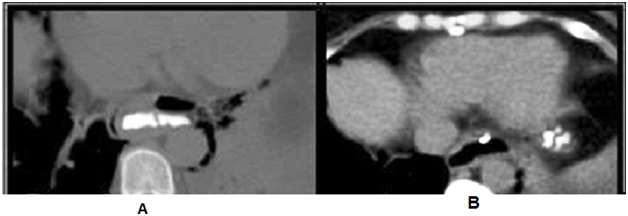

A Rigiflex balloon dilator (Boston Scientific, Boston, MA, USA) with a diameter of 30mm was used under endoscopic control for pneumatic esopha­geal dilatation. She was fine after PD a part from mild chest pain. In the next day the patient started to complain from increasing severity of her chest pain. A Multislice post contrast CT scan of the chest and abdomen with oral contrast showed a Leaking oral contrast is seen along the left side of the termination of the dorsal esophagus (Figure 1).

Figure 1 Contrast enhanced CT scan of the chest and abdomen with oral contrast showed a Leaking oral contrast is seen along the left side of the termination of the dorsal esophagus.

Another upper endoscopy was done and a distal tear was visualized at the distal end (Figure 2), Over-the-scope clip (OTSC) was used to close this tear (Figure 3) (Video). After the closure of the oesophageal, tear with OTSC, CT gastrografin was performed which showed minimal oesophageal leakage (Figure 4).

Figure 4 Contrast enhanced CT showing the oesophageal leakage before (A) and after closure of the tear (B) the leakage became minimal.